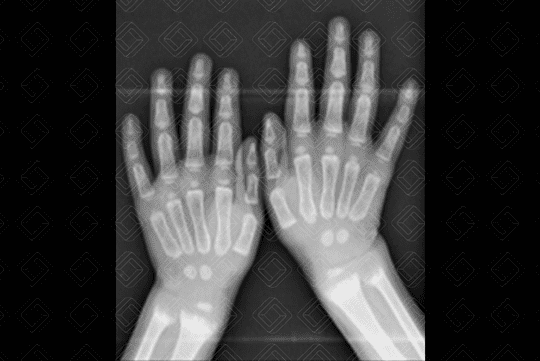

Descrição da lesão: Radiografia dos membros superiores e mãos (figuras 1 e 2). Alargamento das fendas epifisárias e metafisárias da ulna e rádio, bilateralmente. As metáfises apresentam aspecto franjeado. Osteopenia difusa. Estes achados radiológicos são típicos do raquitismo.